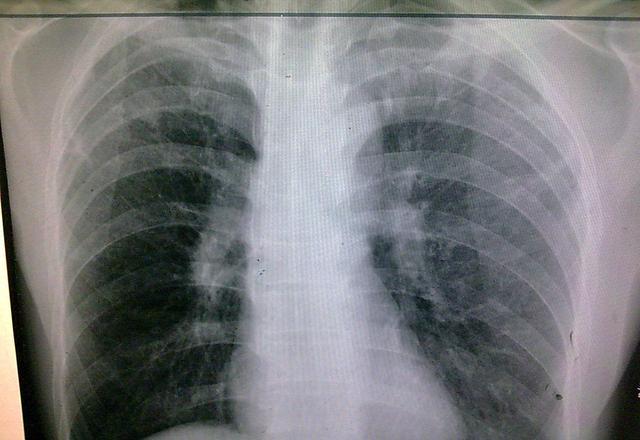

肺结核咳出坏死物图片

肺结核

空洞型肺结核

肺结核ct

肺结核图片

肺结核x光片